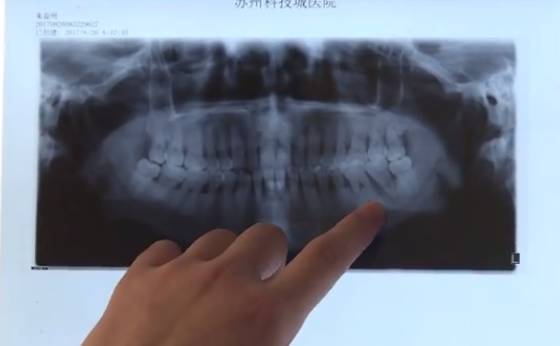

圖片來源于百姓關注

朱先生由于牙周炎發作,沒有重視,吃藥治療也是斷斷續續,直到后來在醫院掛水時,醫生發現他整個脖子都已經腫了起來。經過檢查,朱先生因為牙周炎反復發作,已經引起牙周牙髓聯合病變,兩個顎下間隔全部都感染了, 通過及時手術,切開脖子排膿,才避免了生命危險。